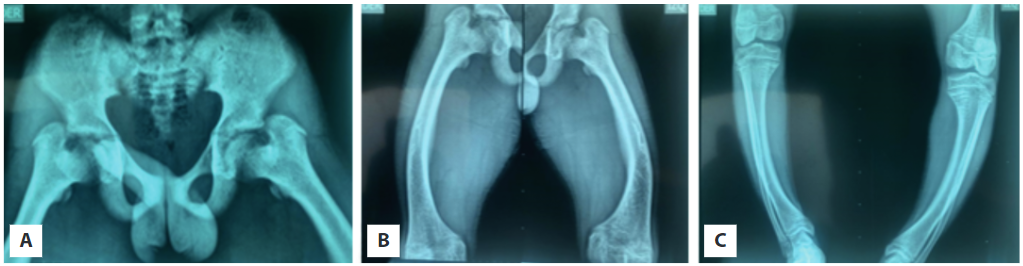

Por su genu varo se solicita además radiografías de cadera y huesos largos (Figura 2), con hallazgos compatibles de raquitismo. Se solicita ecografía renal y vías urinarias con las que se descarta nefrocalcinosis. Sin olvidar el diagnóstico clínico y radiográfico del raquitismo hipofosfatémico, endocrinología pediátrica inicia manejo con sales de fosfato y calcitriol.

El FGF-23 induce la pérdida renal del fosfato al suprimir la expresión de cotransportadores sodio-fosfato (NaPi-2a y NaPi-2c) en la superficie apical del túbulo proximal de la nefrona, condicionando el desarrollo de hiperfosfaturia (11). FGF-23 también inhibe la acción de la 1α-hidroxilasa, necesaria para el paso de 25-Hidroxivitamina D a su forma activa 1,25 dihidroxivitamina D3 (1,25-OH-2D3), e igualmente reduce la absorción del fosfato del intestino y el hueso (12). Una pérdida sostenida de fosfato lleva a una profunda hipofosfatemia, alteración bioquímica fundamental que puede estar presente desde el nacimiento o después de los 6 meses de vida (13). Cuando aparece, se retarda el crecimiento esquelético y, en ocasiones, la edad ósea (14). Manifestaciones clínicas como talla baja y las lesiones óseas raquíticas son hallazgos fenotípicos característicos que están presentes en los pacientes de nuestro reporte, aunque su gravedad es muy variable entre los individuos que presentan esta entidad. En este reporte se observa claramente cómo el impacto social y económico puede influir en la vida de estos pacientes, al producir secuelas físicas y un compromiso psicológico muy evidente en el niño que ocasionan la desescolarización. Las radiografías de los huesos largos del paciente pediátrico exhiben una mineralización disminuida en medio de trabéculas escleróticas gruesas, ensanchamiento de metáfisis y arqueamiento de las piernas (14). Las enfermedades dentales como los abscesos radiculares, antecedentes presentes en la madre del joven, a menudo se desarrollan debido a los defectos en la dentina y el esmalte (15). Sin terapia, el crecimiento lineal se desacelera entre los 4 o 5 años de edad, presentándose talla baja evidente en la madre y el hijo (5,14). La entesopatía mineralizante y la osteoartropatía con frecuencia se desarrollan en la edad adulta (5).

A nivel radiológico se encuentra una pérdida de la definición y nitidez de la línea metafisaria distal con desflecamiento o “deshilachamiento”, pseudofracturas en la cara lateral de ambos fémures; asociados a la hipofosfatemia se observa disminución en la RTP y TmP/GRF. A pesar de existir una importante gravedad clínica, cabe anotar que los niveles séricos del fosfato en el niño no descendieron proporcionalmente, incluso con previas elevaciones en fosfatasa alcalina, lo que corresponde con los diversos fenotipos de la enfermedad. Además, es importante resaltar la ausencia de dichas características en otros familiares, por lo que se considera que se trata de una probable mutación espontánea en la madre y que ha sido trasmitida a su hijo.